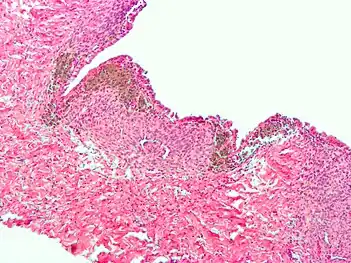

Histopathology

For a histopathological diagnosis, at least two of the following three criteria should be present:[110]

- Endometrial type stroma

- Endometrial epithelium with glands

- Evidence of chronic hemorrhage, mainly hemosiderin deposits

Immunohistochemistry has been found to be useful in diagnosing endometriosis as stromal cells have a peculiar surface antigen, CD10, thus allowing the pathologist go straight to a staining area and confirm the presence of stromal cells and sometimes glandular tissue is identified that was missed on routine H&E staining.[111]

Micrograph showing endometriosis (right) and ovarian stroma (left)

Micrograph of the wall of an endometrioma. All features of endometriosis are present (endometrial glands, endometrial stroma and hemosiderin-laden macrophages).